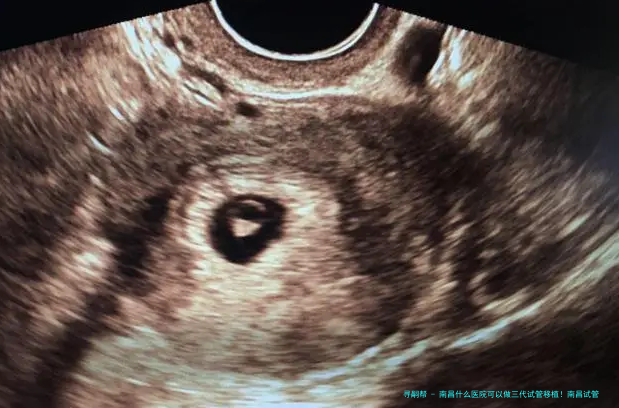

三代试管移植技术是辅助生殖技术中的先进手段,主要用于解决精子健康状况差、卵子质量问题以及遗传性疾病等方面的生育难题。 通过严格的胚胎检查筛选和遗传检测,可以提高成功率,同时减少因遗传不足导致的子孙健康风险。 三代试管移植技术的使用为许许多多家庭提供了生育希望。

1. 咨询及检查: 患者需进行初步咨询和身体检查,了解自身的身体状况,以便制定合适的治疗方案。 此阶段花费大约为2000元左右。2. 促排卵治疗: 根据医生的指示,患者需要接受促排卵治疗,以促进卵子成熟。 这部分费用约为7500元左右。3. 促排卵及胚胎培养: 医生会进行促排卵手术,将成熟的卵子取出后与精子受精,形成胚胎。 此阶段费用大约为12800元左右。4. 胚胎移植: 将筛选后的优质胚胎移植到女性体内,完成整个试管移植过程。 该步骤的花费约为15000元左右。移植过程:

1. 宫颈扩张: 医生会使用仪器将子宫颈扩张,以便胚胎顺利进入子宫腔内。2. 胚胎移植: 将选择好的胚胎通过细长管导入子宫内。整个过程只需几分钟时间。3. 观察和监测: 移植后,需要定期进行孕激素水平监测,确保胚胎着床成功。总结